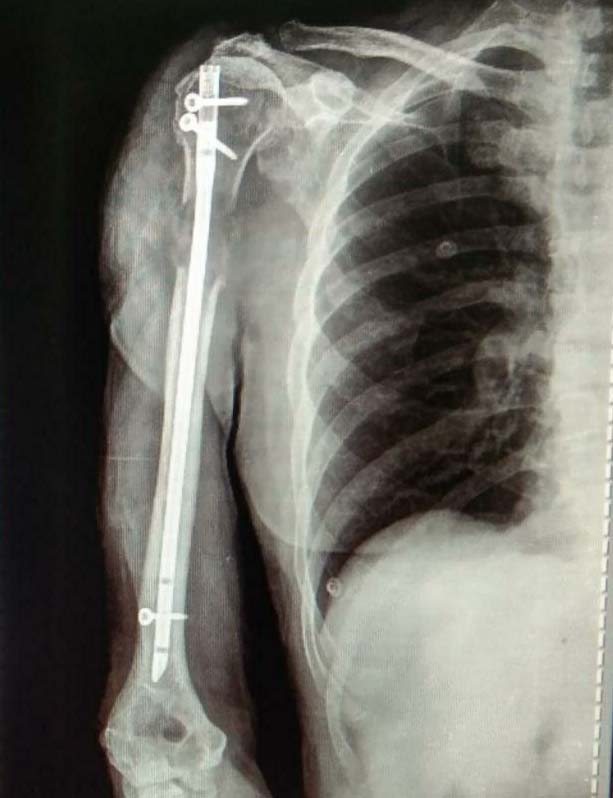

Trauma Fracture